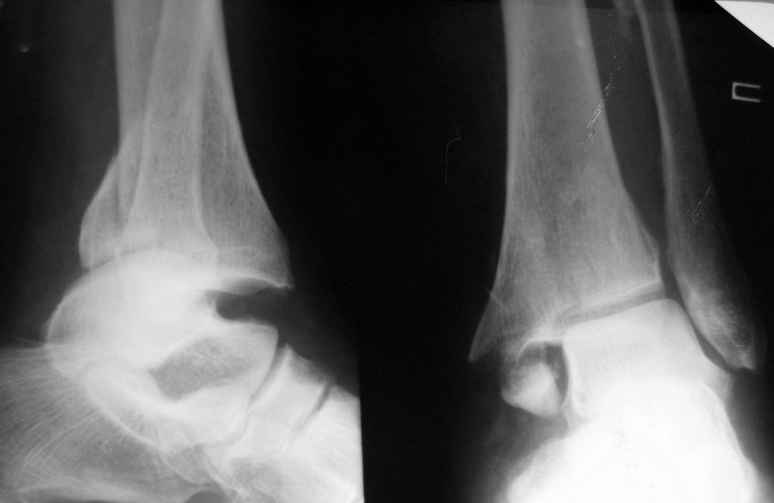

Уважаемые коллеги нужна  помощь в определении тактики лечения:

Больная  Р.,1952 года рождения получила травму  18 августа  2007

года. 31 августа 2007 года была оперирована в другой области по

поводу  DS Закрытого двухлодыжечного перелома правой голени с

подвывихом стопы кнаружи , кзади. Разрыв  дистального межберцового

синдесмоза. Перелом заднего края  большеберцовой кости справа.

Поступила в наше отделение со швами ,с некрозом  медиальной

поверхности правого голеностопного сустава. Проведено  : снятие швов

,  антибиотики , некрэктомия с последующей кожной пластикой

.Заживление 20 декабря 2007 года ,выписана из стационара . 3 марта

2008 года поступает с  гиперемией , отек , флюктуацией. В настоящее

время имеется рана по медиальной поверхности правой голени ,отеки  и

гиперемия  сохраняется .Наша тактика:1) снятия воспалительного

процесса, 2) удаление металлоконструкции, 3) выполнения артродеза

правого голеностопного сустава.